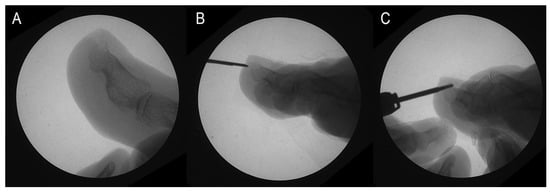

Additionally, the podiatrist objectively assessed each patient’s pain and categorized them into two groups: those who reported pain and those who did not. Patients with dorsal osteophytes who reported pain were advised to consider surgery for osteophyte removal during their initial visit (Figure 2A). After receiving comprehensive information about the available treatment options—including surgery and less invasive, non-definitive alternatives such as conservative management with orthotics or nail treatments—patients were given the autonomy to choose the approach they felt was most suitable. Surgery was recommended based on clinical factors such as symptom severity and lack of improvement with conservative treatments. However, some patients chose to avoid surgery due to personal preferences or a preference for less invasive options, a decision that was respected as part of the shared decision-making process with the medical team.

The surgery was performed according to the protocol outlined in [17] during the second visit, following these steps:

• A 2–4 mm incision was made using a Beaver-64-MIS scalpel on the distal surface wall of the toe, parallel to the longitudinal axis of the toe, followed by drilling of the osteophyte (Figure 2B).

• The contour of the osteophyte was defined using a blunt elevator to avoid damaging the nailbed.

• Osteotripsy was performed using medial and lateral movements of a mini-Shannon drill (Figure 2C).

• Pressure was applied with a surgical spoon to remove the bone paste resulting from the drilling.

Figure 2. Osteotripsy performance. (A) Surgical image. (B) Incision with no. 64 Beaver scalper. (C) Distal phalax osteotripsy.